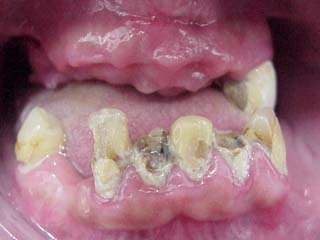

Als erstes wurde im Oberkiefer ein Provisorium mit Klammern eingesetzt. Im Unterkiefer wurde ein Geschiebe mit Steg und Kunststofflager hergestellt. Die Unterkieferzähne konnten trotzdem sie so schlimm aussahen noch gerettet und überkront werden.

Wie oft schon habe ich in meiner Zahnarztpraxis Zahnarzt München von verzweifelten Patienten gehört aus Scham über Jahre nicht zum Zahnarzt gegangen zu sein. Erst die ehrlichen Bilder im Internet hätten Ihnen Mut gemacht Ihre Scham zu überwinden. Viele glaubten wohl die einzigen mit schlechten unschönen Zähnen zu sein. Wenn auch manche Menschen über realistische Bilder sehr erschrecken, so hilft es gerade bei Scham über diese Bilder sein Schicksal zu teilen. Als Fallbeispiele wählt man natürlich immer besonders aussagekräftige Bilder. Bei dem Patienten oben abgebildet war auch ich trotz jahrelanger Tätigkeit geschockt. Wenn man aber selbst so einen Fall wieder zu einem guten Ende bringen kann so gibt es sicher vielen Besuchern meiner Homepage Hoffnung.